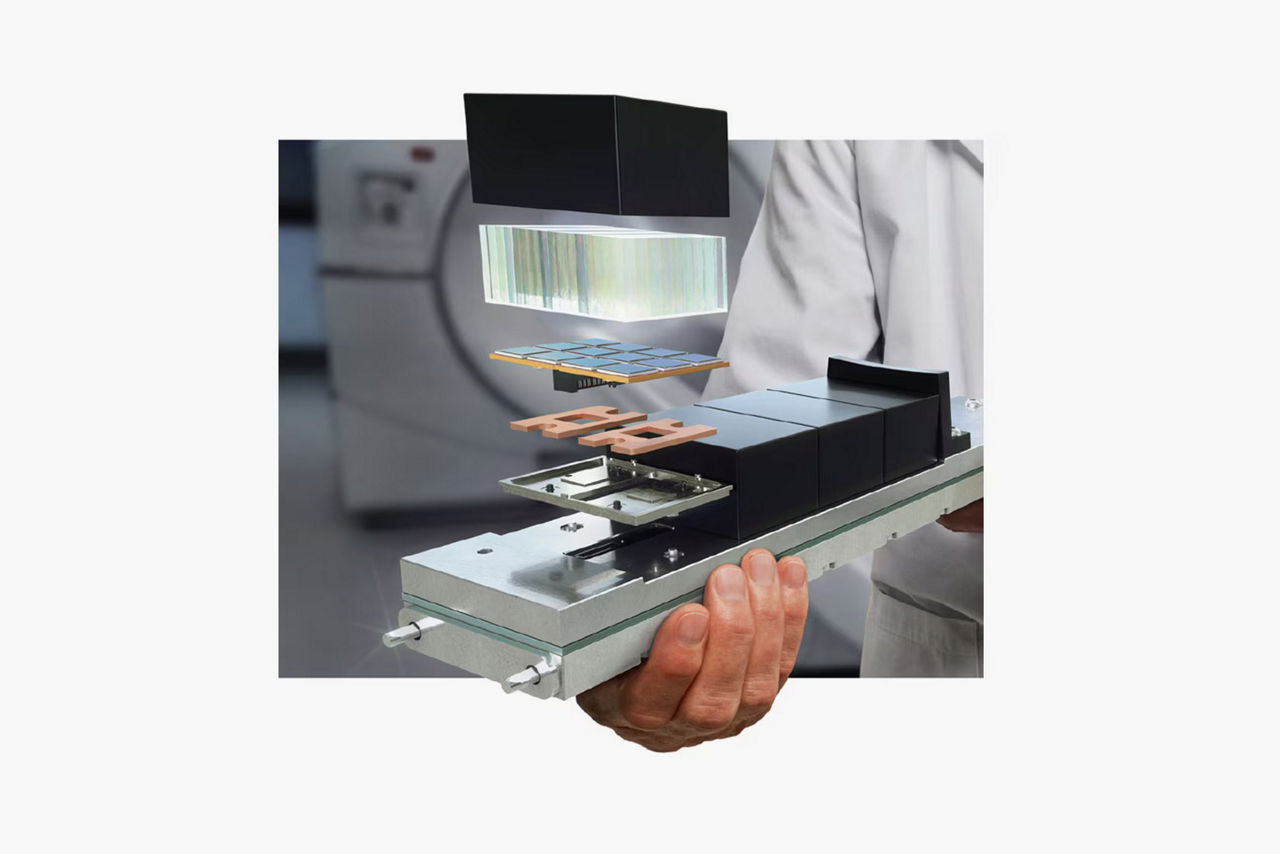

Omni Legend

Discovery IQ Gen 2

Discovery™ MI DR